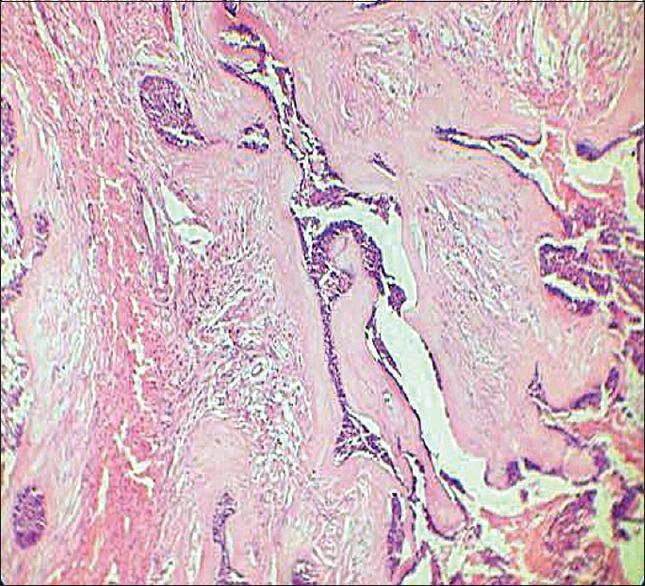

Hybrid ameloblastoma has a variable clinical, radiological, and histopathological presentation. They contain two or more different histologic types and their biologic comportment is still arguable. We herein present a case of a hybrid variant of desmoplastic ameloblastoma which is the first of its kind to have ever been reported due to its unusual location in the maxillary anterior region, along with systematic review of clinicopathologic features of reported cases immunohistochemical markers may act as an adjunct in the accurate diagnosis of these lesions.